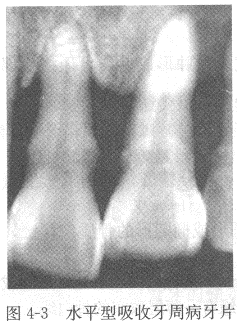

【答案】牙周病主要表现为牙槽骨的吸收破坏,X线片上的骨吸收主要有三种类型:(1)水平型吸收 一组牙齿或全口牙齿的牙槽骨从嵴顶向根尖方向呈水平向高度的减低(图4-3)。

【解析】X线表现 牙周炎主要表现为牙槽骨吸收,牙槽嵴顶及骨硬板模糊、消失,牙槽嵴高度降低。也可表现为牙周膜间隙增宽或缩窄、牙根吸收或牙骨质增生等。牙周炎所引起的牙槽骨吸收有三种类型:

①牙槽骨水平型吸收:表现为牙槽突从嵴顶呈水平方向向根尖方向高度减低